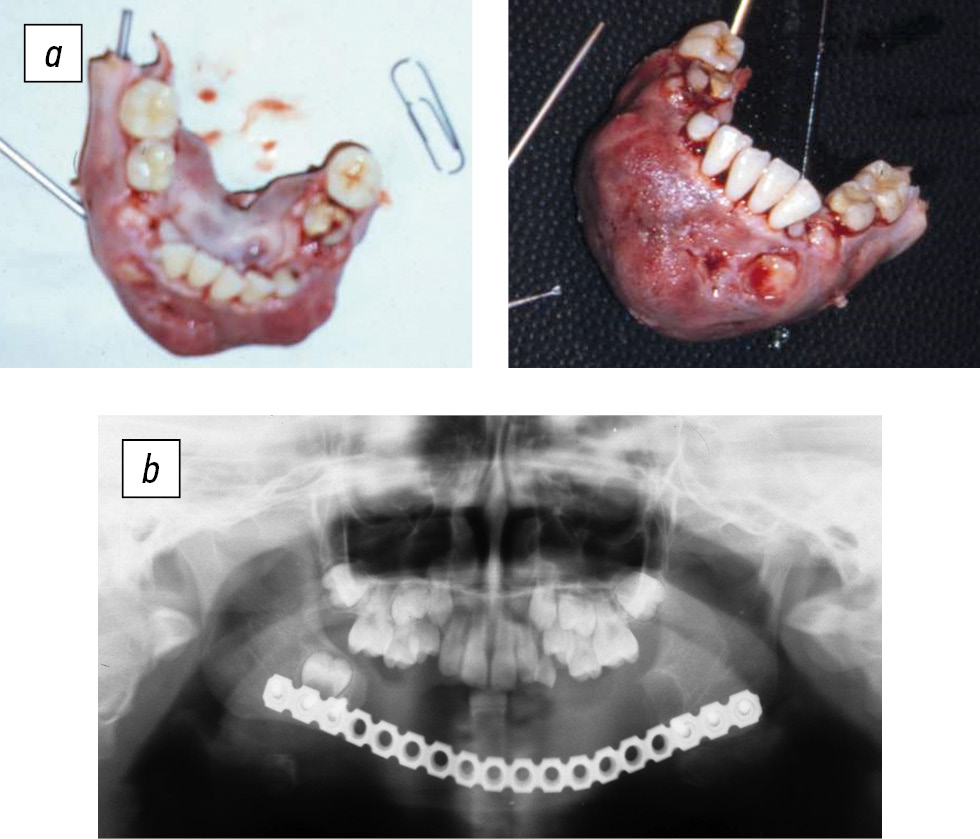

During the primary surgery, the neoplasm was removed in the volume of the affected segment of the jaw and within 8–10 mm of the intact bone tissue. The jaw defect was replaced with a titanium reconstructive plate (endoprosthesis) manufactured by Konmet and fixed on each side with three screws (Fig. 2).

Fig. 2. Patient B (6 years old). Osteoblastoclastoma of the lower jaw: a, resection of the affected area; b, replacement of the jaw defect with a reconstructive plate